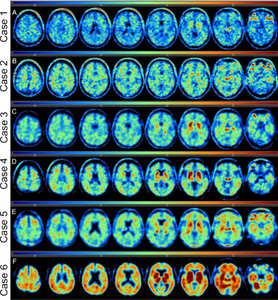

| Associations between near end-of-life flortaucipir PET and post-mortem CTE-related tau neuropathology in six former American Football Players

Researchers studied three former National Football League (NFL) players and three collegiate football players who had flortaucipir and florbetapir PET prior to death. They were then evaluated postmortem for the presence of CTE. They found four of the six were autopsy confirmed CTE and three of these four had met the criteria for traumatic encephalopathy syndrome (TES). One of the players without autopsy confirmed CTE also met the criteria for TES. Researchers concluded that flortaucipir–PET could be useful in detecting high-stage CTE in living persons, although off–target flortaucipir binding in the hippocampus and thalamus can affect the interpretation of testing.